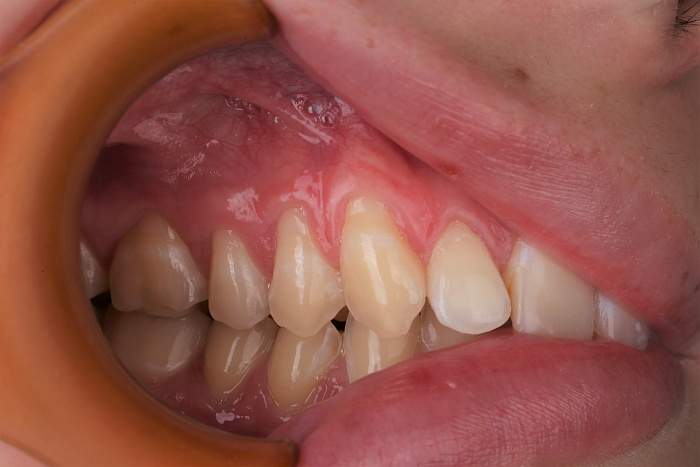

Рецессия десны — это опущение её края, которое приводит к оголению шеек и корней зубов. Этот процесс не связан с инфекцией, но со временем может вызвать повышенную чувствительность и эстетические нарушения.

На начальном этапе рецессия может не вызывать выраженных симптомов, но по мере прогрессирования становится заметным не только эстетический дефект, но и дискомфорт при приёме пищи, обнажение корня, убывание костной ткани. Причинами рецессии могут быть как травмы, так и системные факторы, включая возрастные изменения, особенности строения десны. Единственным эффективным методом устранения рецессии на этапе, когда уже изменена форма десны, является хирургическое вмешательство. Оно позволяет закрыть обнажённый участок корня и восстановить здоровую линию десны.

Результаты работ